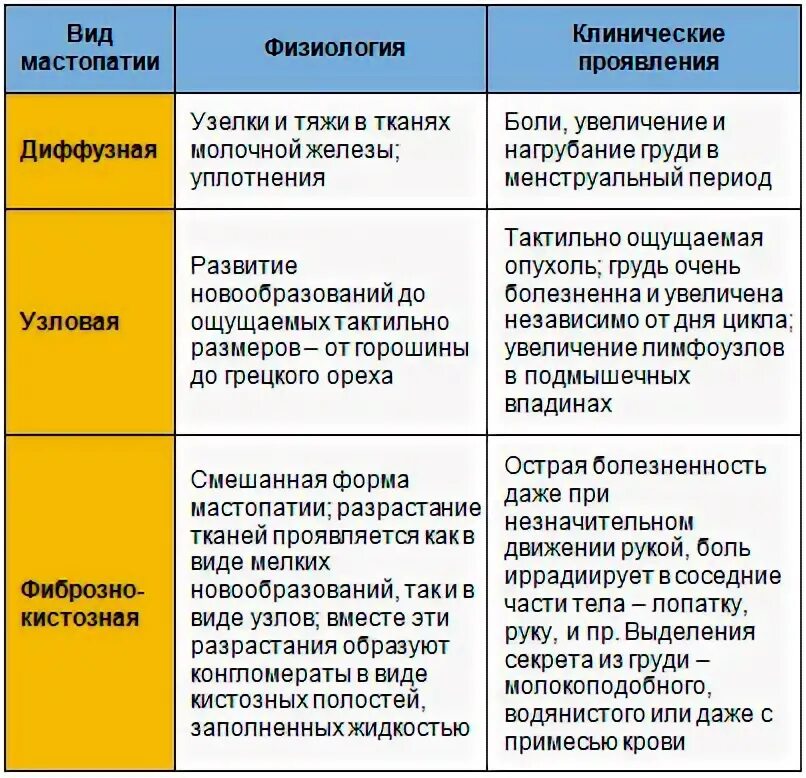

Признаки умеренно выраженной наружная 113 фото